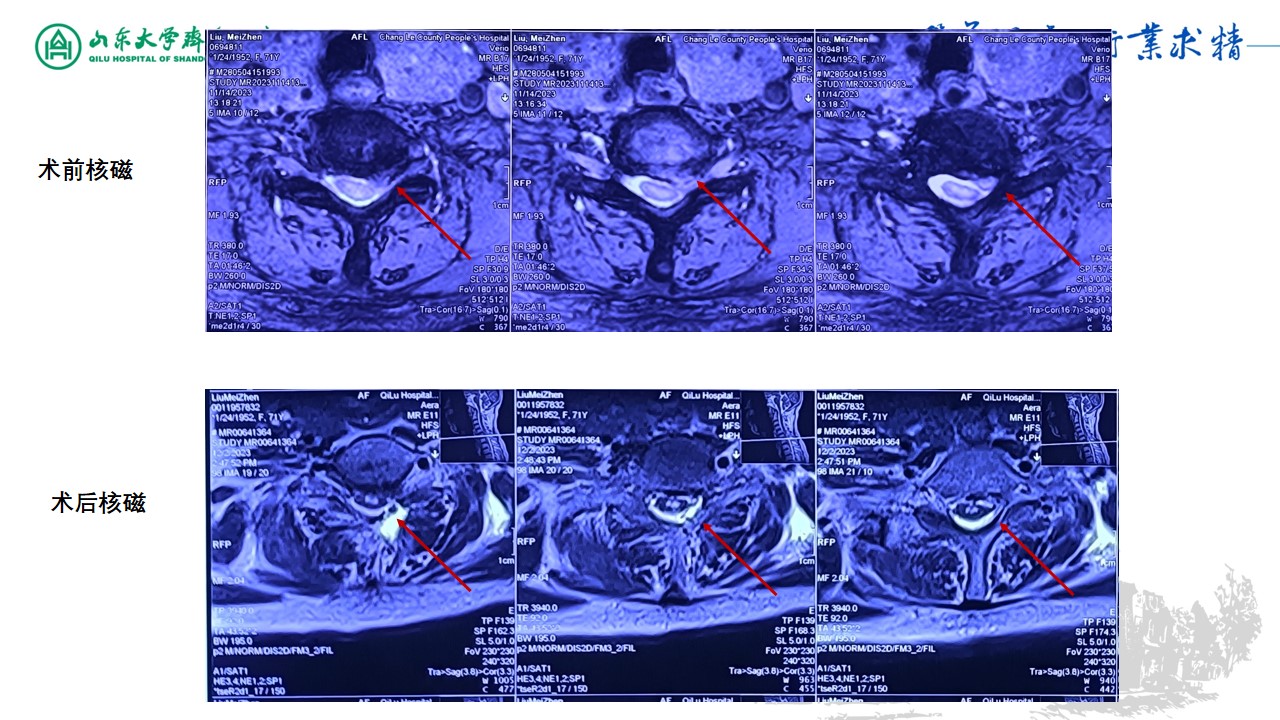

脊柱内镜下颈椎后路椎间孔减压髓核摘除术1例-山东大学齐鲁医院神经外科脊柱脊髓团队